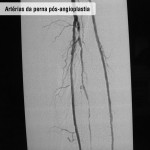

Doença obstrutiva em diabéticos